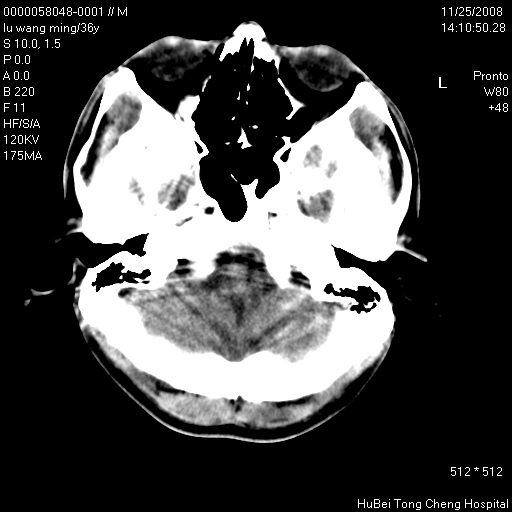

患者 男,36岁。头部烧伤36年伴溃烂,经久不愈。患者几个月大时,倒入火炉不幸烧伤头部,后长期溃烂,经久不愈。

临床诊断:1)头皮烧伤并感染。2)颅骨病损?

颅脑ct轴位平扫(层厚、层距均匀10mm),图像如下:

以骨质破坏为为,边缘呈虫噬样改变,多砂粒样钙钙化或死骨,伴软组织及硬膜外积脓,考虑为结核感染可能性大,建议细菌培养。

额顶局部骨质破坏缺损

患者有明确的病史,且经久不愈,更该考虑软组织化脓性感染,颅骨损害伴硬膜下下积脓

结合病史考虑颅骨慢性骨髓炎

结合病史考虑颅骨慢性骨髓炎伴硬膜外积脓。

骨质破坏,边缘呈虫噬样改变,结合患者明确烧伤史,经久不愈,考虑软组织化脓性感染,颅骨损害伴硬膜下积脓。